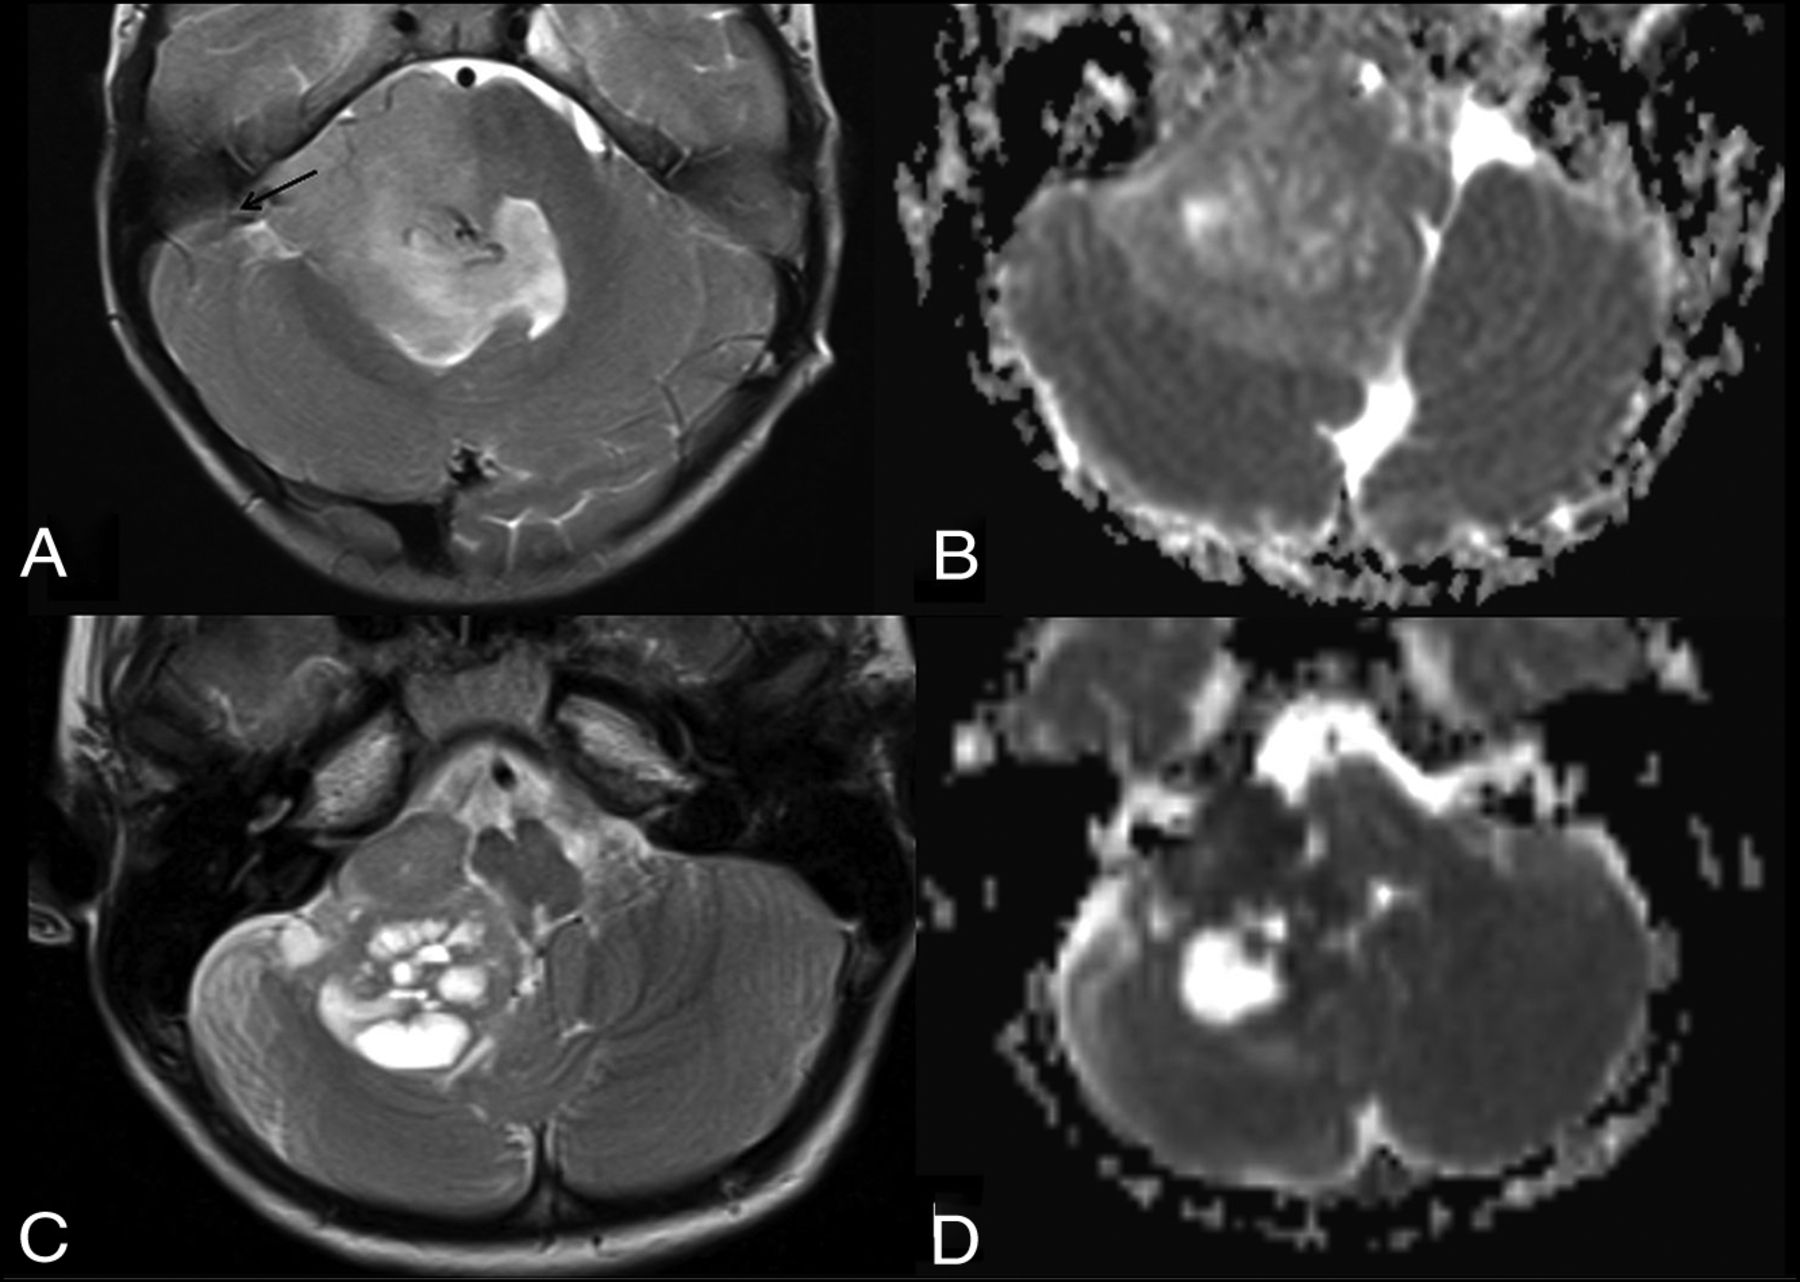

Differential diagnoses in posterior fossa tumors involving the foramen of Luschka and cerebellopontine angle. Axial T2WI (A) and ADC map (B) in a child with ependymoma (flow chart 2, number 423). Note the presence of internal vessels (arrow) and intermediate ADC values. Axial T2 (C) and ADC maps (D) in a 2-year-old boy with a AT/RT (new flow chart number 411). Note very low values of ADC, suggesting an embryonal tumor and peripheral cysts.